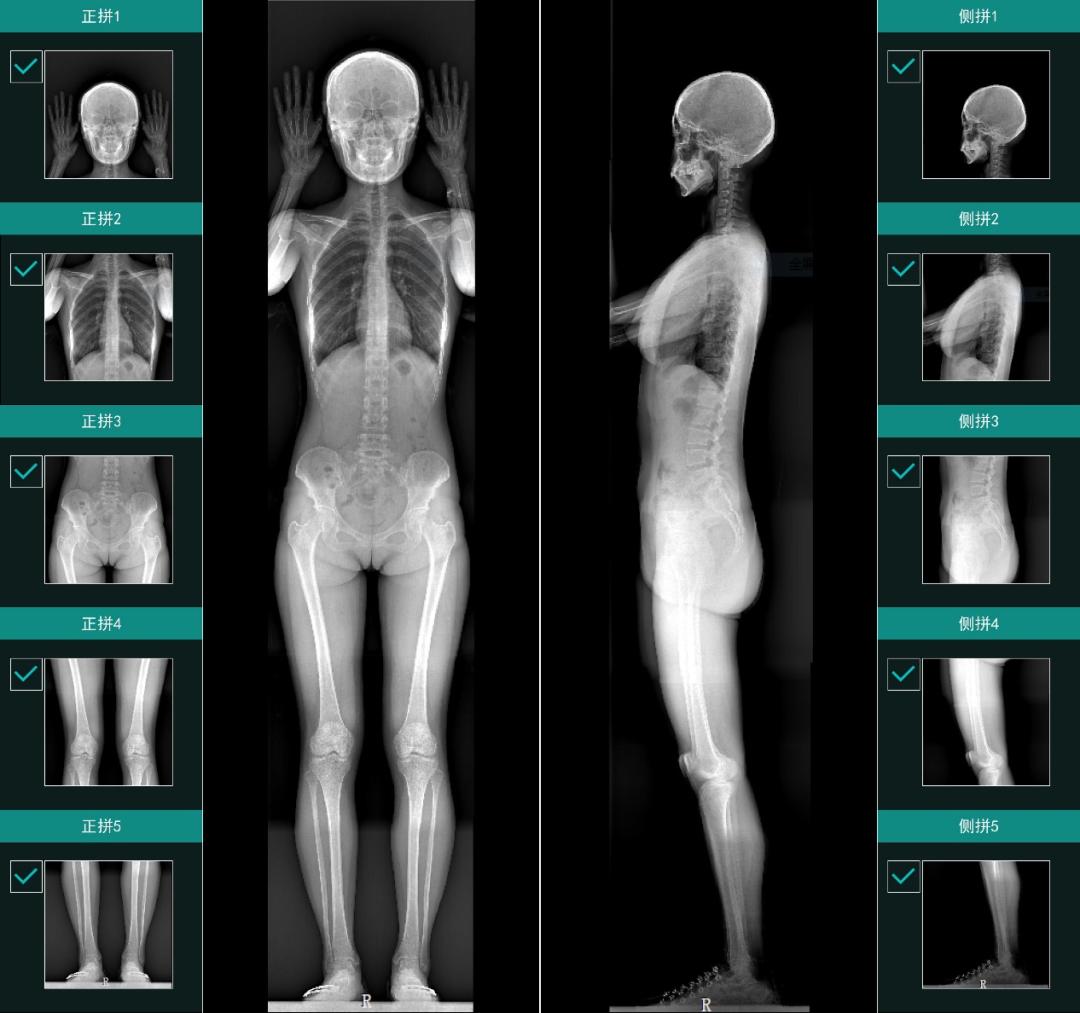

“这段话对我的冲击非常大,我第一次清晰地意识到:原来自己做的这个技术这么有意思。”蔡宗远说道。“我们提出来的x射线立体摄影的概念,就是要能够看到骨关节的运动状态,对运动做评价评分,从而去解决现在骨科诊断与治疗上的限制。”蔡宗远介绍道。

凭借雄厚的科研实力,涛影医疗2019年牵头承担了科技部“十三五”国家重点研发计划数字诊疗装备专项,联合多家知名高校和医院,共同研发国际领先的三维动态全身与关节数字成像及人工智能临床专家系统。次年,公司获批为国家高新技术企业。

2022年7月,由涛影医疗自主研发的全身双平面X射线摄影系统Ti-WISH-IL取得中国医疗器械注册证。截至目前,已有80余家医院签订装机合同,5家医院实现商业装机。